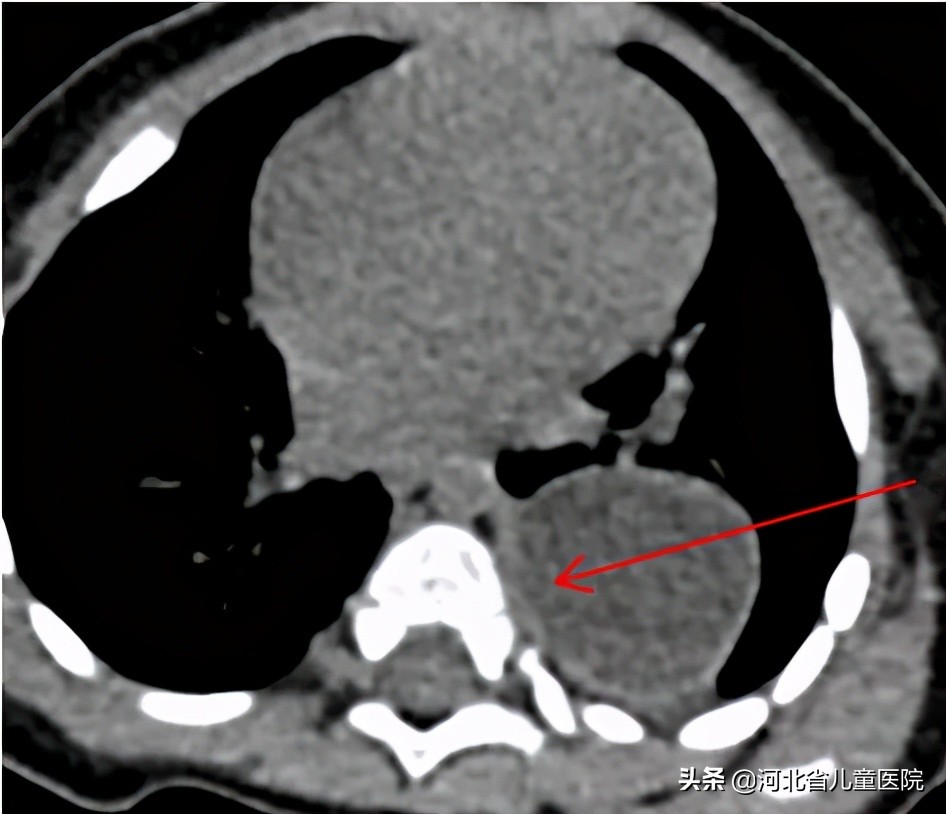

9个月的乐乐,因为咳嗽检查胸部CT,发现存在巨大的纵隔占位,乐乐爸妈很是费解,孩子平时也没啥症状,怎么会纵隔长个东西呢?

所幸,乐乐的纵隔占位经手术切除,术后恢复顺利,病理回报是良性的囊肿,大家悬着的心也终于能放下了。